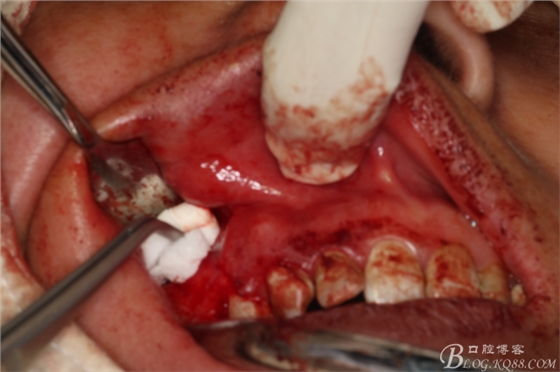

圖10.完整摘除囊壁

圖11.囊壁摘除后,暴露的16腭側(cè)根尖有少許牙膠尖超填

圖12.高速牙鉆截取16腭根3mm.

圖13.刮除腭側(cè)牙根周?chē)∽兘M織

圖14.切去16近中頰根根尖3mm,并行MTA倒充填